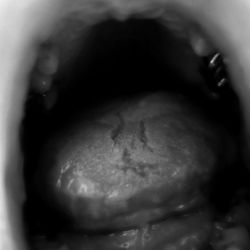

26.4.18 Yves Phelippot

20180426

upj_yvesphelippot

26.4.2018

Voyage à l'intérieur de mon corps.

Yves Phelippot